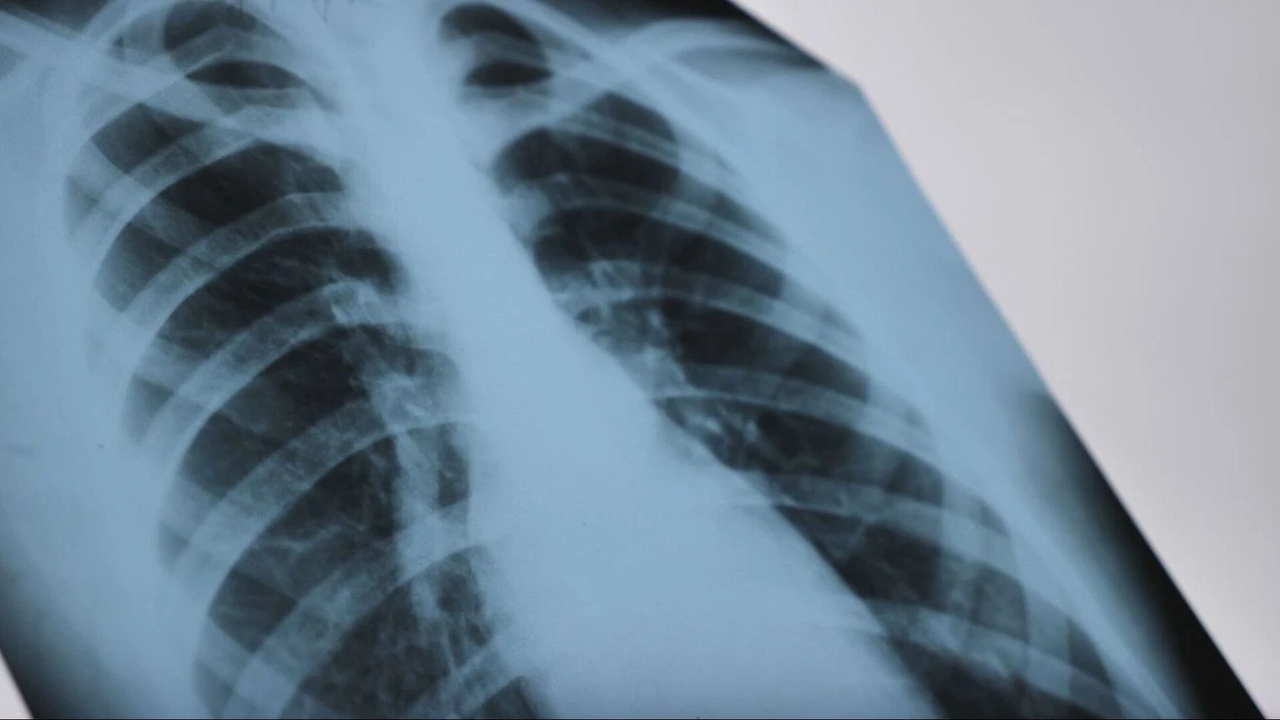

The number of tuberculosis cases in the United States has reached its highest level in over a decade, according to data from the Centers for Disease Control and Prevention. This has raised concerns among infectious disease specialists, as the disease can spread through respiratory droplets. Early testing and immediate-result programs are being launched across the country to prevent transmission. Dr. Stephen Blatt, TriHealth’s medical director for infectious diseases, said that active tuberculosis can be cured with a nine-month course of antibiotics.